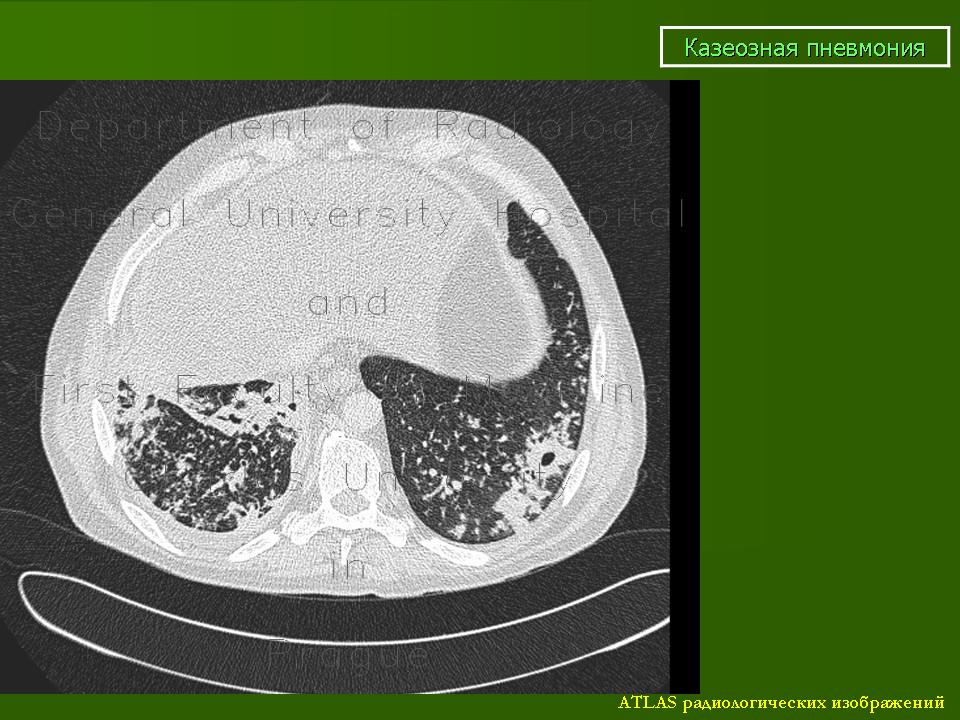

Казеозная пневмония.

КП - одна из самых тяжелых форм ТБ, часто как осложнение ряда других форм; характерен выраженный казеозно-некротический компонент воспаление, быстрое прогрессирование, множественные полости распада, высокая летальность;

Патоморфологически: массовая гибель клеточных элементов и постепенное распространение казеозного некроза (ацинозная - ацинозно-лобулярная - сливная лобулярная - сегментарная КП и т.д.); вследствие гибели клеток ИС и выброса протеолитических ферментов происходит расплавление очагов казеоза с формирование полостей (множественных острых каверн); возможно лимфогематогенное распространение процесса

1. лобарная пневмония: затемнение всей или большей части доли, вначале однородное, затем с участками просветления бухтообразной формы с нечеткими контурами; в дальнейшем видны каверны

2. лобулярная пневмония: крупные очаговые тени и небольшие фокусы (до 1,5 см) неправильной формы, средней или высокой интенсивности, с нечеткими контурами; часто располагаются симметрично

Небольшой пример.

По клинике (острое начало, интоксикация, кровохарканье), рентген-исследованию, и мокрота (Mbt+). К сожалению, информации мало, сам пациента не наблюдал, снимки архивные, 2009 года. Вот все, что смог выжать у очевидцев, то и передал.